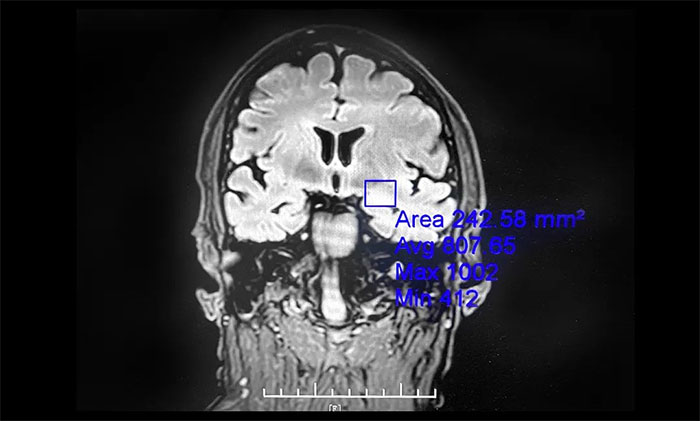

▲ 癲癇外科手術(shù)為癲癇患者帶來希望